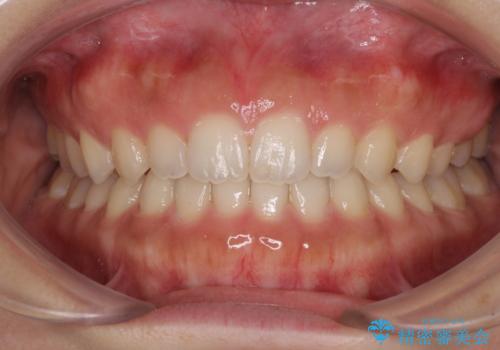

捻れて飛び出した前歯 インビザラインで整った前歯に

歯と歯の間を削ることでうまくスペースコントロールでき、また、毎日22時間以上しっかりとマウスピースを装着していただいたので、スムーズに治療が進みました。

治療途中で転勤となり、遠方からの通院となったため、来院間隔空いてしまいましたが、2年間で終えることができました。